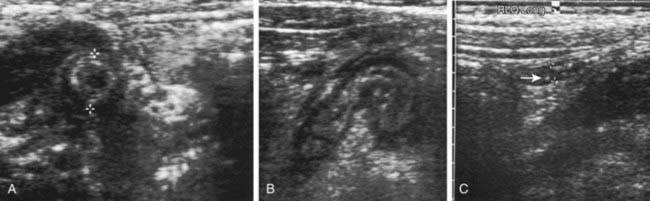

Plain abdominal x-rays can demonstrate several findings in acute appendicitis, including sentinel loops of bowel and localized ileus, scoliosis from psoas muscle spasm, a colonic air-fluid level above the right iliac fossa (colon cutoff sign), or a fecalith (5-10% of cases), but they have a low sensitivity for appendicitis and are not generally recommended (Fig. 335-1). Plain films are most helpful in evaluating complicated cases in which small bowel obstruction or free air is suspected.

image

Figure 335-1 Calcified appendicoliths are seen in a coned-down anteroposterior view of the right lower quadrant (A) and in the resected appendix of a 10 yr old girl with acute appendicitis (B).

(From Kuhn JP, Slovis TL, Haller JO: Caffrey’s pediatric diagnostic imaging, vol 2, ed 10, Philadelphia, 2004, Mosby, p 1682.)